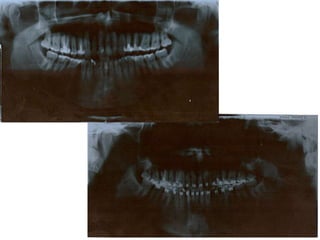

Atresia Maxilar Com Mordida Aberta

Atresia maxilarMordida aberta

anterior